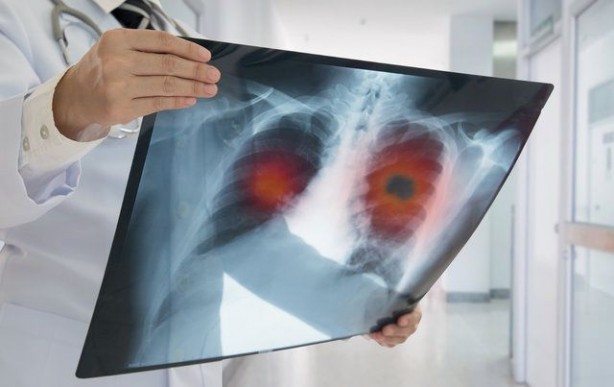

2017-11-16 15:47:27 Geçmeyen öksürük akciğer kanseri belirtisi

Akciğer kanseri hem erkeklerde hem de kadınlarda en sık ölüm nedeni. Sinsi bir şekilde ilerleyen akciğer kanseri bazen belirti vermese de işte dikkatten kaçmaması gereken akciğer kanseri belirtileri... Dünyada ve ülkemizde hızla yaygınlaşan akciğer kanseri erkeklerde prostat, kadınlarda ise meme kanserinden sonra en sık görülen ikinci kanser türü olarak tanımlanıyor. En önemli nedeninin sigara olarak gösterildiği akciğer kanseri; özellikle nefes darlığı, hırıltı, ani kilo kaybı ya da çeşitli ağrılarla kendini gösterebiliyor.